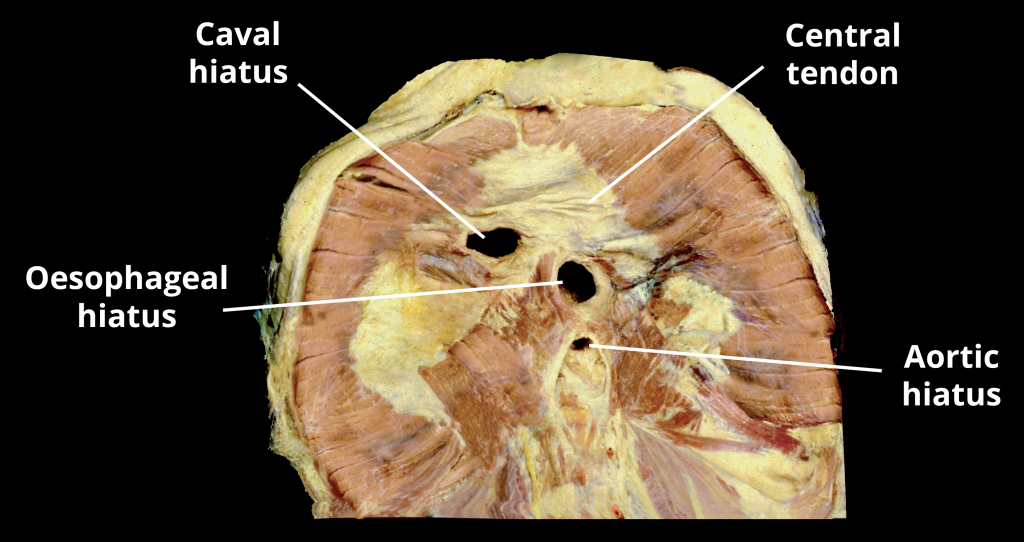

The diaphragm is a double-domed musculotendinous sheet, located at the inferior-most aspect of the rib cage. It serves two main functions: Separates the thoracic cavity from the abdominal cavity (the word diaphragm is derived from the Greek ‘diáphragma’, meaning partition). Undergoes contraction and relaxation, altering the volume of the thoracic cavity and the lungs, producing inspiration and expiration. In this article, we shall look at the anatomy of the diaphragm – its attachments, actions and associated neurovascular structures. Pro Feature - 3D Model You've Discovered a Pro Feature Access our 3D Model Library Explore, cut, dissect, annotate and manipulate our 3D models to visualise anatomy in a dynamic, interactive way. Learn More Anatomical Position and Attachments The diaphragm is located at the inferior-most aspect of the ribcage, filling the inferior thoracic aperture. It acts as the floor of the thoracic cavity and the roof of the abdominal cavity. The attachments of diaphragm can be divided into peripheral and central attachments. It has three peripheral attachments: Lumbar vertebrae and arcuate ligaments. Costal cartilages of ribs 7-10 (attach directly to ribs 11-12). Xiphoid process of the sternum. The parts of the diaphragm that arise from the vertebrae are tendinous in structure, and are known as the right and left crura: Right crus – Arises from L1-L3 and their intervertebral discs. Some fibres from the right crus surround the oesophageal opening, acting as a physiological sphincter to prevent reflux of gastric contents into the oesophagus. Left crus – Arises from L1-L2 and their intervertebral discs. The muscle fibres of the diaphragm combine to form a central tendon. This tendon ascends to fuse with the inferior surface of the fibrous pericardium. Either side of the pericardium, the diaphragm ascends to form left and right domes. At rest, the right dome lies slightly higher than the left – this is thought to be due to the presence of the liver. By TeachMeSeries Ltd (2025) Fig 1The diaphragm is split into two lobes, left and right. Note the vertebral attachments of the diaphragm are the left and right crura. Pro Feature - Dissection Images Prosection of the demonstrating the inferior surface of the diphragm. Prosection of the demonstrating the inferior surface of the diphragm. You've Discovered a Pro Feature Access our Dissection Image Library Enhance your understanding with high-resolution dissection images showcasing real-life anatomy. Learn More Pathways through the Diaphragm The diaphragm divides the thoracic and abdominal cavities. Thus, any structure that pass between the two cavities will pierce the diaphragm. There are three openings that act as conduit for these structures: Caval Hiatus (T8) Oesophageal Hiatus (T10) Aortic Hiatus (T12) Inferior vena cava Terminal branches of right phrenic nerve Oesophagus Right and left vagus nerves Oesophageal branches of left gastric artery/vein Aorta Thoracic duct Azygous vein A tip for remembering the vertebral levels: vena cava has eight letters (T8), oesophagus has ten letters (T10), and aortic hiatus has twelve letters (T12). By TeachMeSeries Ltd (2025) Fig 2View of the inferior surface of the diaphragm. Note the three openings. Actions The diaphragm is the primary muscle of respiration. During inspiration, it contracts and flattens, increasing the vertical diameter of the thoracic cavity. This produces lung expansion, and air is drawn in. During expiration, the diaphragm passively relaxes and returns to its original dome shape. This reduces the volume of the thoracic cavity. Innervation and Vasculature The halves of the diaphragm receive motor innervation from the phrenic nerve. The left half of the diaphragm (known as a hemidiaphragm) is innervated by the left phrenic nerve, and vice versa. Each phrenic nerve is formed in the neck within the cervical plexus and contains fibres from spinal roots C3-C5. The majority of the arterial supply to the diaphragm is delivered via the inferior phrenic arteries, which arise directly from the abdominal aorta. The remaining supply is from the superior phrenic, pericardiacophrenic, and musculophrenic arteries. The draining veins follow the aforementioned arteries. By TeachMeSeries Ltd (2025) Fig 3The anatomical course of the phrenic nerves, which innervate the diaphragm. Clinical Relevance Paralysis of the Diaphragm Diaphragmatic paralysis is due to an interruption in its nervous supply. This can occur in the phrenic nerve, cervical spinal cord, or the brainstem. It is most often due to a lesion of the phrenic nerve: Mechanical trauma: ligation or damage to the nerve during surgery. Compression: due to a tumour within the chest cavity. Myopathies: such as myasthenia gravis. Neuropathies: such diabetic neuropathy. Paralysis of the diaphragm produces a paradoxical movement. The affected side of the diaphragm moves upwards during inspiration, and downwards during expiration. A unilateral diaphragmatic paralysis is usually asymptomatic and is most often an incidental finding on x-ray. If both sides are paralysed, the patient may experience poor exercise tolerance, orthopnoea and fatigue. Lung function tests will show a restrictive deficit. Management of diaphragmatic paralysis is two-fold. Firstly, the underlying cause must be identified and treated. The second part of treatment deals with symptomatic relief. This is usually via non-invasive ventilation, such as a CPAP (continuous positive airway pressure) machine. By Ratnayake et al [CC BY 2.0] via BioMed Central Ltd Fig 4Chest x-ray, showing paralysis of the right hemidiaphragm. Do you think you’re ready? Take the quiz below Pro Feature - Quiz The Diaphragm Question 1 of 3 Submitting... Skip Next Rate question: You scored 0% Skipped: 0/3 1800 More Questions Available Upgrade to TeachMeAnatomy Pro Challenge yourself with over 1800 multiple-choice questions to reinforce learning Learn More Rate This Article